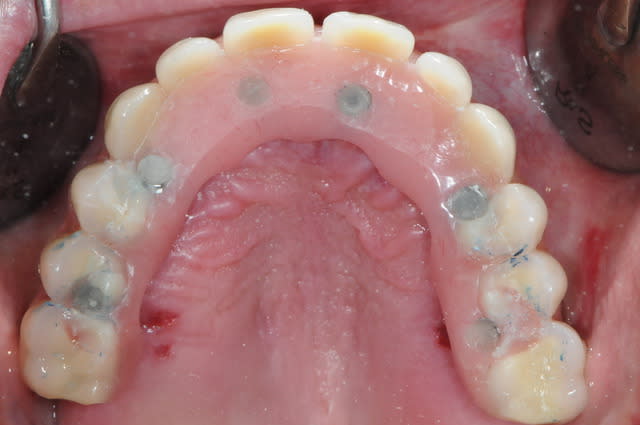

depuis que je me suis acheté une imprimante 3D, je fais moi même mes guides chirurgicaux.

j'ai trouvé ça il y a quelques mois avec l'intention de réaliser des petits objets pour les gamins et des guides pour mes chirurgies.

voici un cas en images, j'espère que ça plaira, ça fait un moment que je n'ai rien posté sur nonol et suis en manques de critiques et de compliments.

la patiente a été opérée hier et j'ai mis ses prothèses aujourd'hui.

la veille de l'intervention j'ai imprimé le model 3 D.